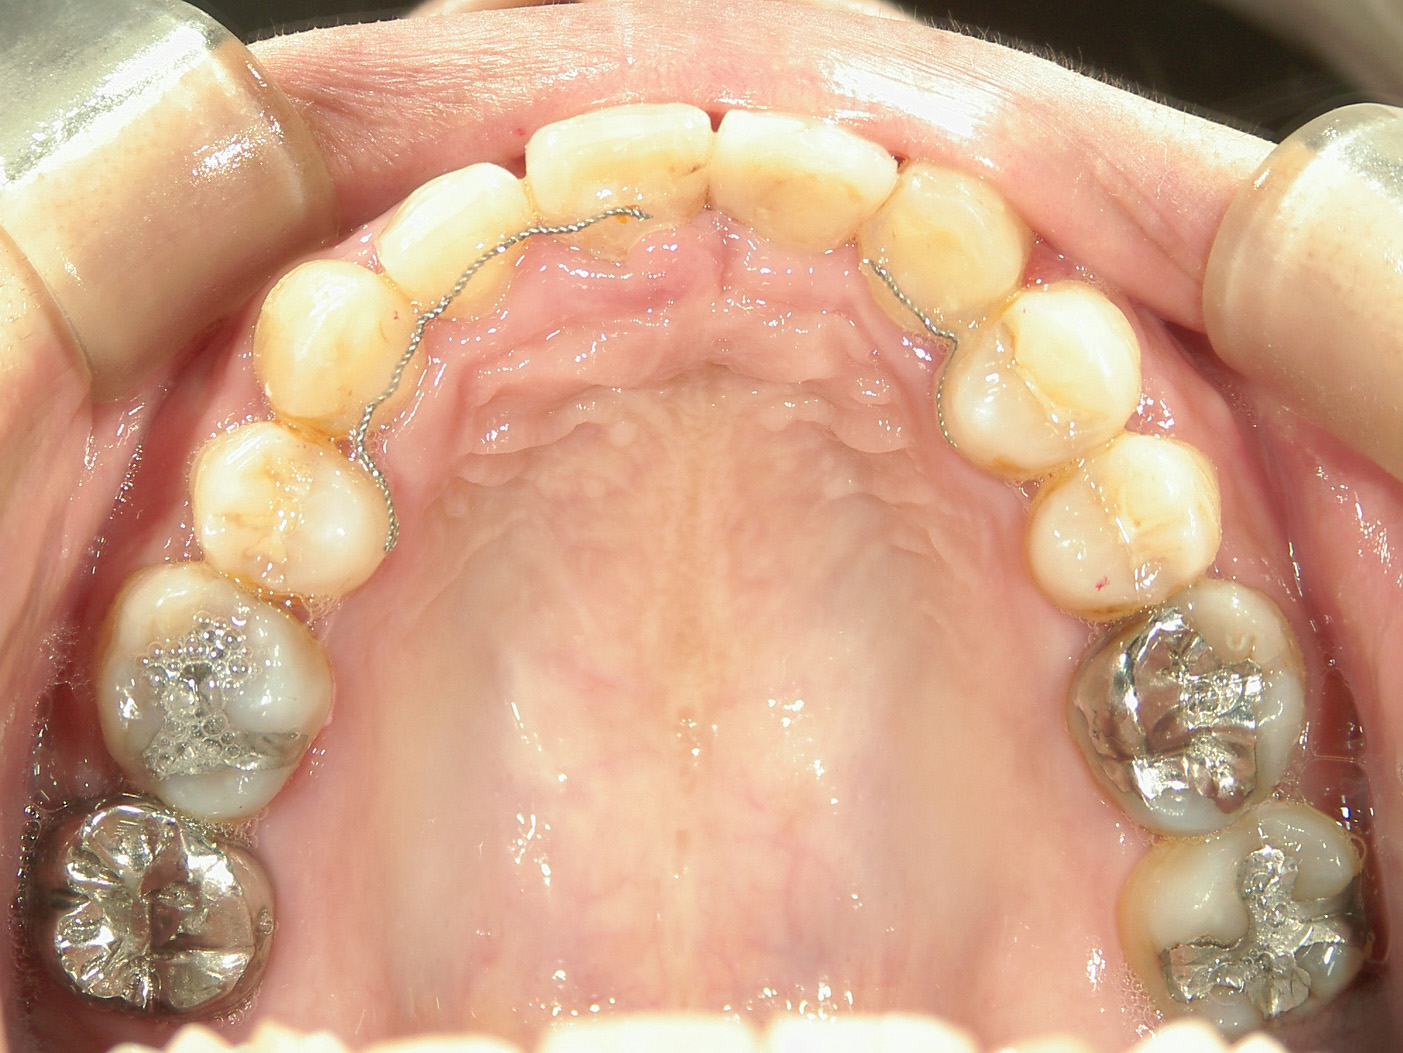

右上中切歯 抜歯後、空隙を閉鎖しました。

歯根の移動後、元々の中切歯の形に硬質レジンで歯冠を形態修正しました。

・抜歯した右上前歯の隣りの歯を抜歯してあいたスペースで移動。

・右上犬歯を移動して、開いたスペースへ移動。

・右上 第一小臼歯を移動して犬歯のスペースへ移動。